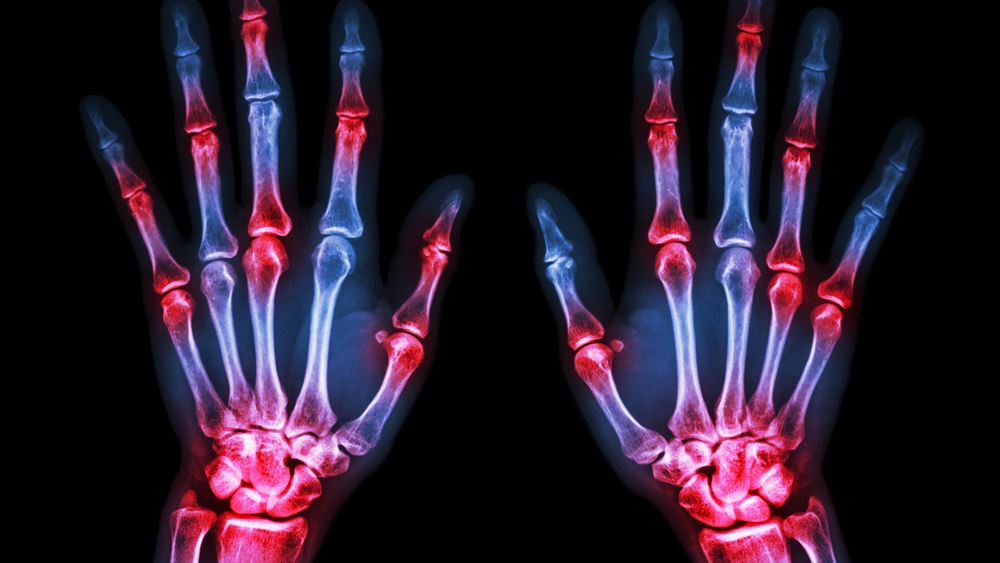

Σημαντική έγκριση νέας θεραπείας για τους ασθενείς με ρευματοειδή αρθρίτιδα

Η έγκριση του upadacitinib από την Ευρωπαϊκή Επιτροπή για ασθενείς με μέτρια έως σοβαρή ρευματοειδή αρθρίτιδα είναι ένα από τα τελευταία “καλά νέα” της χρονιάς για ασθενείς με τη συγκεκριμένη νόσο. “Σχεδόν 3 εκατομμύρια άνθρωποι στην Ευρώπη ζουν με ρευματοειδή αρθρίτιδα, η πλειονότητα των οποίων δεν επιτυγχάνει ύφεση και ενδέχεται να υποφέρει από πόνο, κόπωση, πρωινή δυσκαμψία στις αρθρώσεις και εξάρσεις”, δήλωσε ο Καθηγητής Ronald van Vollenhoven, M.D., Ph.D., Κέντρο Ρευματολογίας και Ανοσολογίας του Άμστερνταμ στις Κάτω Χώρες. “Όπως διαπιστώνεται στο μεγάλο αυτό πρόγραμμα κλινικών μελετών Φάσης 3 στη ρευματοειδή αρθρίτιδα, το upadacitinib έχει τη δυνατότητα να βελτιώσει σημαντικά τα σημεία και τα συμπτώματα της νόσου και να βοηθήσει περισσότερους ασθενείς να πετύχουν ύφεση ή χαμηλή ενεργότητα της νόσου”.